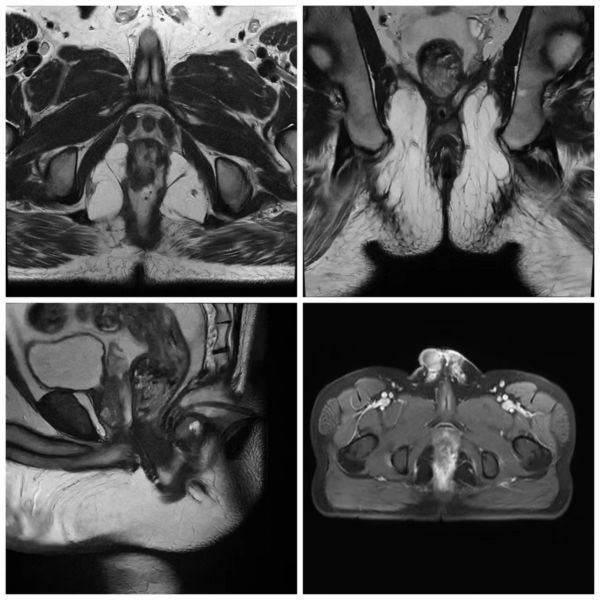

患者杜某,男,41岁。2021年6月因“反复肛周疼痛伴流脓流液7个月”就诊普四科,既往有外院肛瘘切除手术及2型糖尿病病史数年,未规范治疗糖尿病。收住院后,完善肛管M R I增强检查、结肠镜、结核等相关术前常规检查,排除合并IBD、结核及肿瘤。因患者原发病灶位于内外括约肌间,随着感染的扩散,脓肿沿括约肌间由“U型马蹄形”脓肿发展为“X型蝴蝶形”脓肿,且脓腔内有较多气体,直肠可见破溃口,考虑合并直肠瘘。同时,因脓肿波及范围广,脓腔及分支瘘管较多,一次手术无法达到痊愈目的,且对肛门括约肌损伤大,术后直接会影响肛门形态及功能,甚至可能导致术后排便失禁。

第一次手术前肛管MRI图